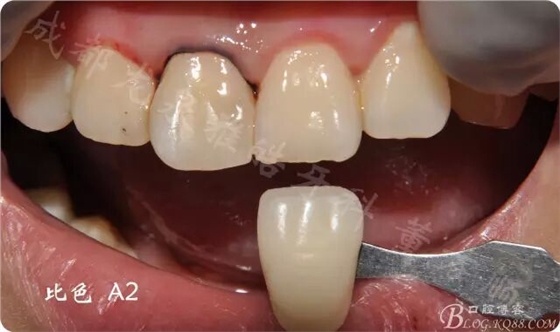

2周后復(fù)診 行瓷貼面修復(fù)

比色